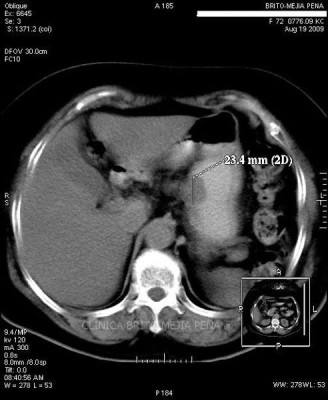

Pseudoquiste páncreas axial